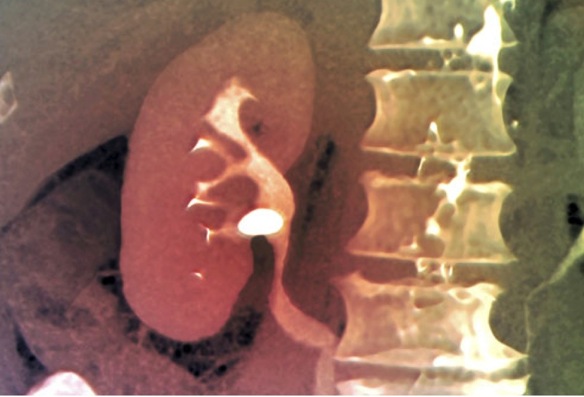

Para confirmar el diagnóstico se emplean pruebas de imagen, que nos permiten confirmar la existencia, tamaño y localización de las litiasis. La ecografía es el medio más empleado, muchas veces acompañada de radiografías con/sin contraste (urografía intravenosa o TAC). En ocasiones son necesarias analíticas complementarias o endoscopias.

renal